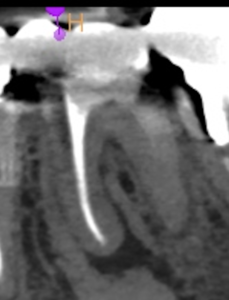

#19 Re-RCT 1yr recall(2026.1.13)

#19

MB

ML

D

術前に大きな根尖病変が存在していたM根のそれは消失はしていないが大幅に縮小し、

術前に根尖病変がなく再根管形成・充填しなかったD根はやはり依然として根尖病変はできていない。

このケースでも

Selective Root Canal Retreatmentが奏功している。

ということで根尖病変は完全消失はしていないのでまた1年後に経過を見せてもらうことになった。